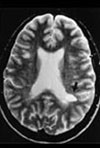

Myelencephalon-spesifikk protease (MSP) finnes i sentralnervesystemet hos voksne. Enzymet letter tilgangen av inflammatoriske celler til hjernen, og i store mengder kan det føre til økt destruksjon av vev. Forskere ved Mayo-klinikken i Minnesota, USA har publisert viktige funn vedrørende MSP-enzymet (1), funn som kanskje kan føre til nye behandlingsmuligheter ved multippel sklerose. I lesjoner fra mennesker med multippel sklerose, og i lesjoner fra dyremodeller av sykdommen, fant forskerne svært høye nivåer av MSP, særlig i T-celler og makrofager. Disse celletypene finnes vanligvis i store mengder nær demyeliniserte områder. In vitro - studier med rekombinant MSP viste blant annet at enzymet kan bidra til tap av utvekster på oligodendrocyttene, cellene som produserer myelin.

– Dersom det viser seg at dette enzymet bidrar vesentlig til demyeliniseringen, kan en hemning av enzymet tenkes å føre til redusert skade på nervevevet, sier Kjell Morten Myhr, som er leder av Det nasjonale kompetansesenter for multippel sklerose ved Haukeland Sykehus.

– Det er imidlertid usikkert hvorvidt mengden MSP er økt ved alle typer vevsskade, eller om dette er spesielt for multippel sklerose. Oligodendrocytter har til en viss grad potensial til å nydanne myelin. En «naken» nerveutløper (akson) kan dermed få gjendannet myelinskjeden. Det kan tenkes at man ved å hemme MSP kan fremme danningen av nye utvekster på oligodendrocyttene og dermed stimulere remyeliniseringen. Remyelinisering er særlig viktig i en tidlig fase av sykdommen.